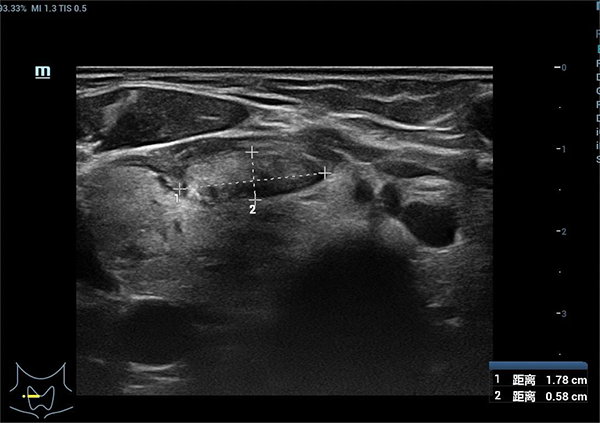

术后3个月,甲状腺右叶囊实性结节缩小至1.78cm*0.58cm

栾玉爽为她制定了详细的治疗方案,从准备工作到消融结束才短短30分钟。术后,刘女士自觉肿物消退,压迫感消失,观察半小时后自行回家。术后三个月,患者肿物明显缩小,缩小率达93%。